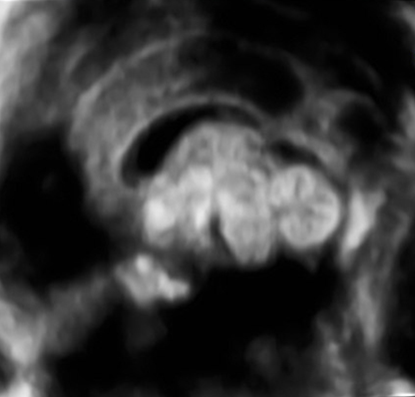

产科_胎儿颅脑_颅脑正中矢状面:正常胼胝体和小脑蚓部